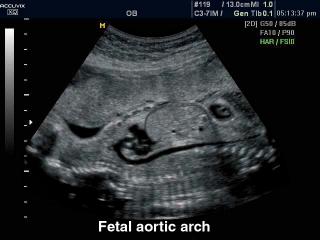

В разделе "Акушерство" атласа представлены результаты ультразвуковых исследований беременных на разных сроках. Здесь вы можете посмотреть изображения внутренних органов, мозга, сердца и пола плода, эхограммы многоплодной беременности, кровотока в плаценте и пуповине, пороков развития и др.